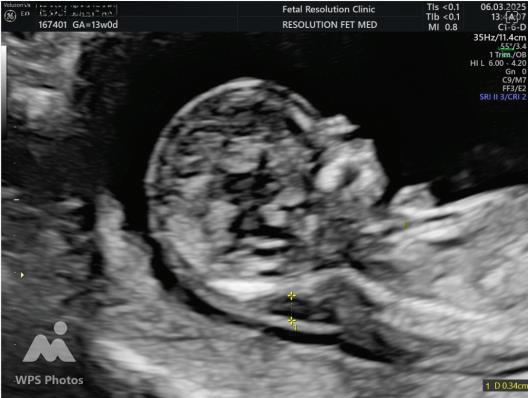

2. NUCHAL TRANSLUCENCY (NT) SCAN

• Done @11–13+6 weeks.

• CRL 45–84 mm.

• This is the cornerstone of first trimester screening.

1. NT is the sonographic appearance of subcutaneous accumulation of fluid behind the fetal neck, below the skin in the first trimester of pregnancy.

2. Measured in mid-saggital section only.

3. Measured between 11-14 weeks.

4. CRL between 45-84mm.

5. Magnified to include only head and upper thorax.

6. Fetus should be in neutral position.

7. Demostrate fetus separate from amnion.

8. Measurement should be ON to ON (cross bar of the callipers should be such that it’s hardly visible and merges with white line, not nuchal fluid).

During the scan more than one measurement should be taken and maximum value should be considered.

INCREASED NT:

1. Aneuploidies

2. Structural Anamolies

3. Genetic Syndromes

4. Fetal infections

5. Metabolic disorders